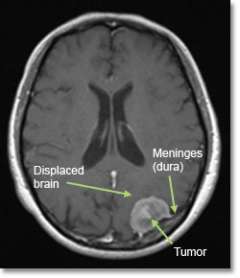

MRI of a meningioma tumor

MRI image showing a typical meningioma tumor

A meningioma is a tumor that arises from a layer of tissue (the meninges) that covers the brain and spine.

Meningiomas grow on the surface of the brain (or spinal cord), and therefore push the brain away rather than growing from within it. Most are considered “benign” because they are slow-growing with low potential to spread.